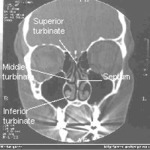

ENS refers to persons who have had surgery where the shelves on the side of the nose called turbinates, have been removed and now the nasal chamber is ‘empty”. Symptoms include nasal pain, loss of sen...